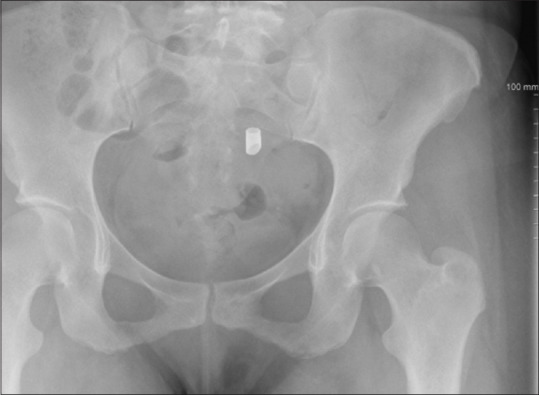

Abstract: This case report describes the dynamics of the detachment of the ceramic beak of an Iglesias resectoscope that was lost in the uterine cavity during 'cold loop' hysteroscopic myomectomy. Our aim is to increase awareness of this issue and caution our colleagues against using Iglesias resectoscopes for hysteroscopies. The ceramic beak of an Iglesias resectoscope can detach itself if hard tissue is encountered during operative hysteroscopy.

Abstract Image